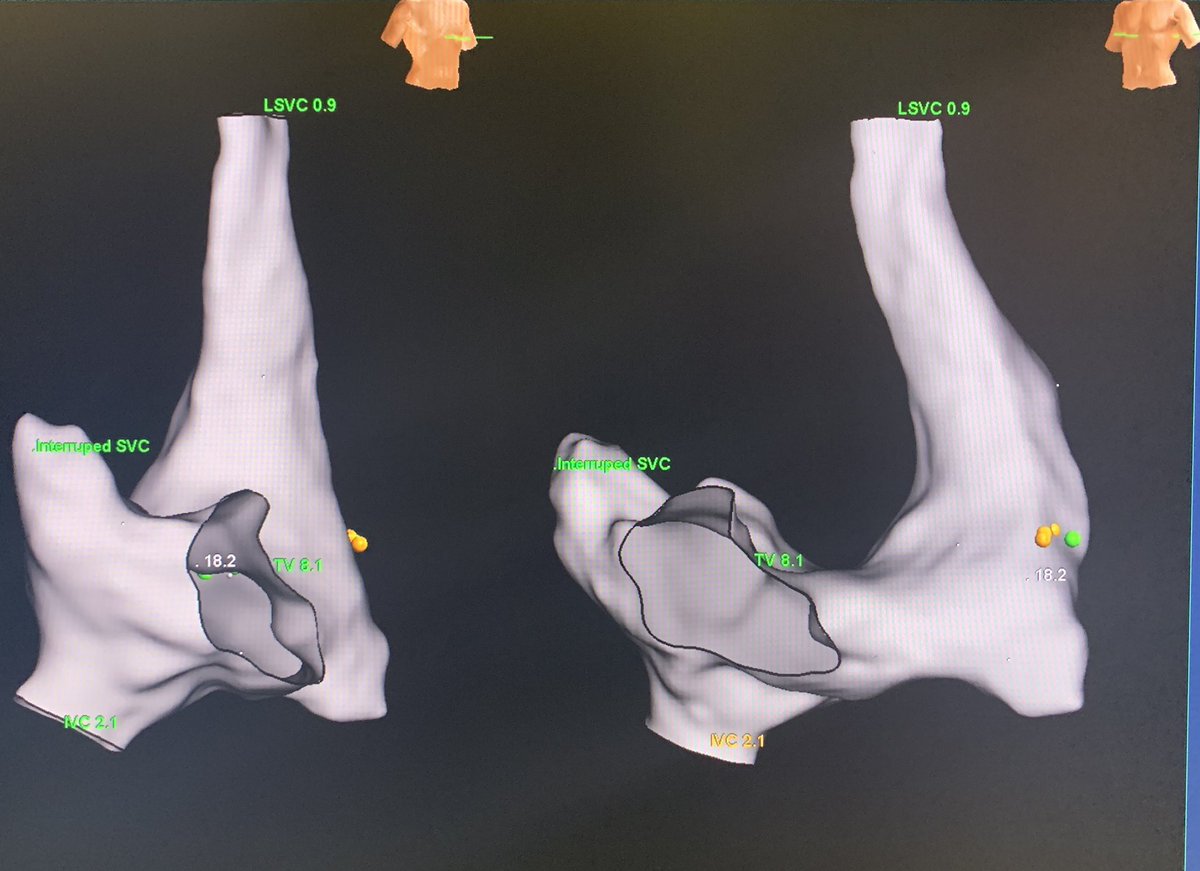

PLSVC is common; PLSVC w/o right SVC (isolated SVC) and a GIANT coronary sinus isn’t. This aneurysmal CS is like another cardiac chamber. Flutter termination in a patient with history of CABG. #mapmoreburnless #EPeeps #HDGrid #atypicalflutter #JustATypicalDayinEP @ArHeartHospital

MonicaYLo's tweet image. PLSVC is common; PLSVC w/o right SVC (isolated SVC) and a GIANT coronary sinus isn’t. This aneurysmal CS is like another cardiac chamber. Flutter termination in a patient with history of CABG. #mapmoreburnless #EPeeps #HDGrid #atypicalflutter #JustATypicalDayinEP @ArHeartHospital